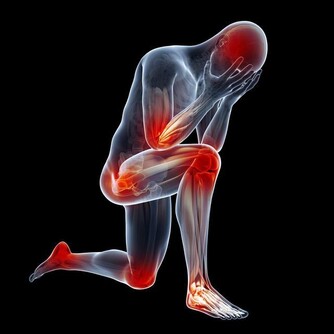

2、健康隱患。生病也是會導致噩夢的,如果長時間做同一個噩夢,夢到我們身體的某個部位,那可以預示著這個部位可能有問題,自己要多去注意。